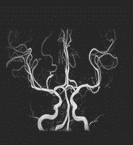

MRI(磁気共鳴画像装置)を導入致しました。

MRI検査により、今まで分からなかった脳の病変が、

簡単に見つけられるようになりました。

(頚部の血管画像)

画像提供:東芝メディカルシステムズ株式会社様